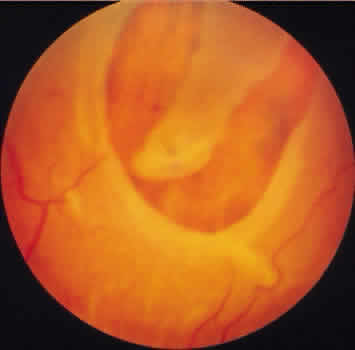

DEGENERATIVE RETINOSCHISIS

Degenerative retinoschisis, a more extensive trophic process, presents as a round or ovoid area of retinal splitting with a smooth fusiform elevation of the inner layer (Fig. 17). The schisis is surrounded on all sides by typical cystoid degeneration; the retinal pillars of the cystoid degeneration as well as the broken pillars near the margin of the schists are prominent. Vessels are located in the inner retinal layer, the intraretinal cavity is optically empty, and the outer retinal layer is moderately irregular in contour.13,14

Fig. 17. Typical degenerative retinoschisis.Note extensive region of typical cystoid degeneration with a rounded and elevated posterior margin. In the center (arrow), radial columns are randomly disrupted, causing a disturbance in coarse surface pattern. (× 18.)

In one type of degenerative retinoschisis, the thin inner wall is composed of the internal limiting membrane, the nerve fiber layer, and retinal vessels (Fig. 18). The irregular outer wall contains portions of the inner nuclear, outer plexiform, outer nuclear, external limiting, and rod and cone layers. At the margin of the cavity, the retinoschisis blends with typical cystoid degeneration and may be relatively flat. Lesions with this appearance have been termed typical degenerative retinoschisis.

Typical degenerative retinoschisis is present in 1% of adult patients and is bilateral in 33% of these patients; therefore, it is evident in 0.7% of adult eyes (see Table 3), with a predilection for location in the inferior temporal quadrant. A narrow band of typical cystoid degeneration is always present between the ora serrata and the anterior border of the schisis cavity; the involved area may extend to or somewhat posterior to the equator.

On clinical examination, typical degenerative retinoschisis appears as round or ovoid areas of retinal splitting with fusiform elevation of the inner layer (Fig. 19). The stippled pattern of surrounding typical cystoid degeneration extends on the inner layer for a variable distance; centrally the inner layer, which contains the blood vessels, is thin and smooth. On contact lens ophthalmoscopy, the inner layer is finely textured, some of the retinal vessels are attenuated, and there is a variable number of tiny, glistening, white dot opacities on the vitreous side. The outer layer, found external to the optically empty cavity, is best seen with indirect ophthalmoscopy when it becomes white on scleral depression. It is somewhat uneven, giving an appearance of finely hammered or beaten metal. Typical degenerative retinoschisis does not extend posteriorly to threaten the macula, and it is not often associated with breaks in either retinal layer; it rarely requires treatment.

Fig. 19. Clinical appearance of typical degenerative retinoschisis: diagram of involved area and ocular fundus photographs showing optic disc, macula, and posterior portion of schisis. Within the schisis and adjacent to the margin is coarse stippling related to broken retinal pillars.